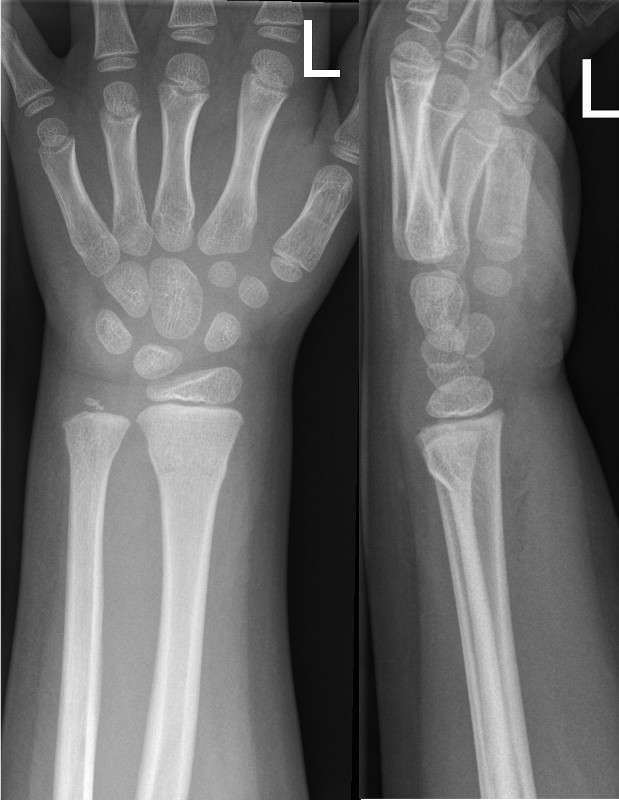

Simple dorsal buckle fracture of the distal radius and ulna with minimal dorsal angulation

Simple dorsal buckle fractures must have ALL of the following features:

- No involvement of the volar surface

- Less than 15 degrees dorsal angulation

- No cortical breach

- Involves the distal third of the radius

- No greenstick or complete fracture of the ulna (buckle of the ulna is acceptable)